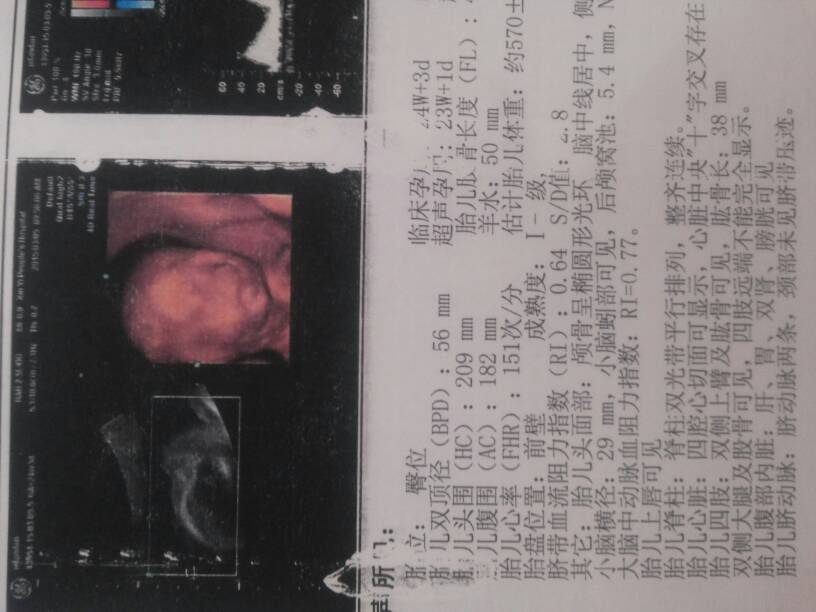

四维顺利归来,能看出男宝女宝吗?纯属好奇 四维顺利归来,能看出男宝女宝吗?纯属好奇 点击展开 庆雯 2015-03-05 15:24 为您推荐: 其他回答 看不出来呀 蜜色遗忘 2015-03-05 17:25 看不出,,, 染指红颜醉 2015-03-05 16:38 不可能看得出来的 荥洋嘛嘛 2015-03-05 16:11 看不出来的 飞儿_j4Rm 2015-03-05 15:43 那样有心跳的了。你看清楚的好吗? 妙语连珠 2015-03-05 15:35 加载更多 相关问题 刚四维检查归来,但内容与其他宝妈的不太一样 帮忙看看!能看出男宝女宝吗? 四维归来,宝宝很健康!宝妈们看看像男宝女宝!